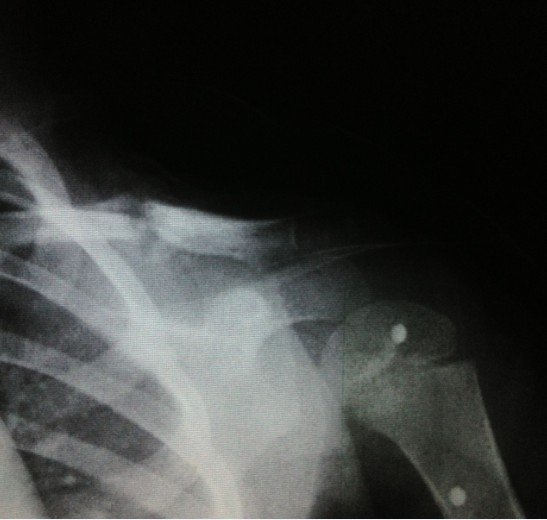

宝宝3岁半出车祸左锁骨骨折

患者信息:女 3岁 贵州 遵义 病情描述(发病时间、主要症状等):2012.10.7日发送车祸,X片确诊为左锁骨骨折。当天就打上八字绷带。想得到怎样的帮助:现在已经自行把八字绷带取下,请问这样做可以吗?因为孩子的腋下已经开始有轻微溃烂的症状(掉干壳壳)前段时间因为出车祸导致孩子的左锁骨骨折,去医院打了八字绷带,刚好一个月去医院复查,医生说已经开始长曾经治疗情况及是否有过敏、遗传病史:无

8字绷带笼殊还是没急着取下来,,才一个月,虽然骨痂生长饥训明显,,骨折断端对位对线也不错, 但仍不能绣殊崭太掉以轻心。再绑一个月估计才可去。 腋下涂点抗生素软膏就行。